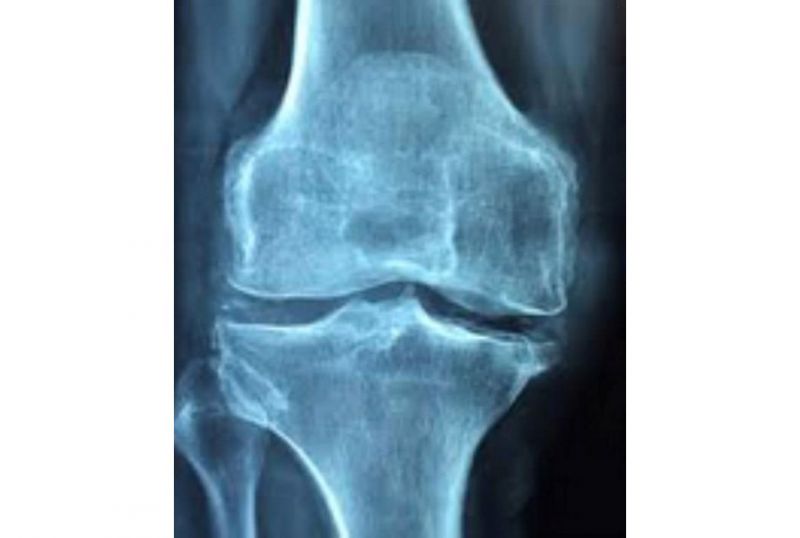

健康人的骨頭堅硬,關節靈活,肌肉收縮,舒緩隨意,行動自然就順暢自如。如果由於某種原因關節發生病變,就會造成局部的腫脹、發熱,活動範圍受限,活動時僵硬、疼痛。引起關節病變的疾病有一百多種,其中最常見的是老年退化性關節炎、運動損傷性關節炎、以及類風濕性關節炎。此外,細菌感染、痛風、遺傳因素、內分泌失調,和其他免疫系統疾病、新陳代謝疾病也會影響關節的健康。

回家後,除了和太太一起看電視,就是吃飯、上網、睡覺。一轉眼就過了50歲,這才赫然發現,怎麼動不動就腰腿痛,而且越來越厲害。每當開車30分鐘以上就疼痛難忍,需要在駕駛座上活動一陣後才能下車。X光檢查顯示他有嚴重的退化性關節炎,右側髖關節和兩側膝蓋都需要做手術。